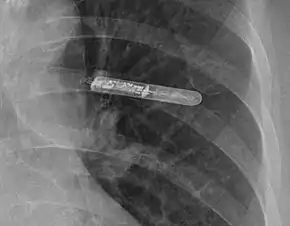

Atrial fibrillation recorded by a Holter monitor

The Holter's most common use is for monitoring ECG heart activity (electrocardiography or ECG). Its extended recording period is sometimes useful for observing occasional cardiac arrhythmias which would be difficult to identify in a shorter period. For patients having more transient symptoms, a cardiac event monitor which can be worn for a month or more can be used.[1]